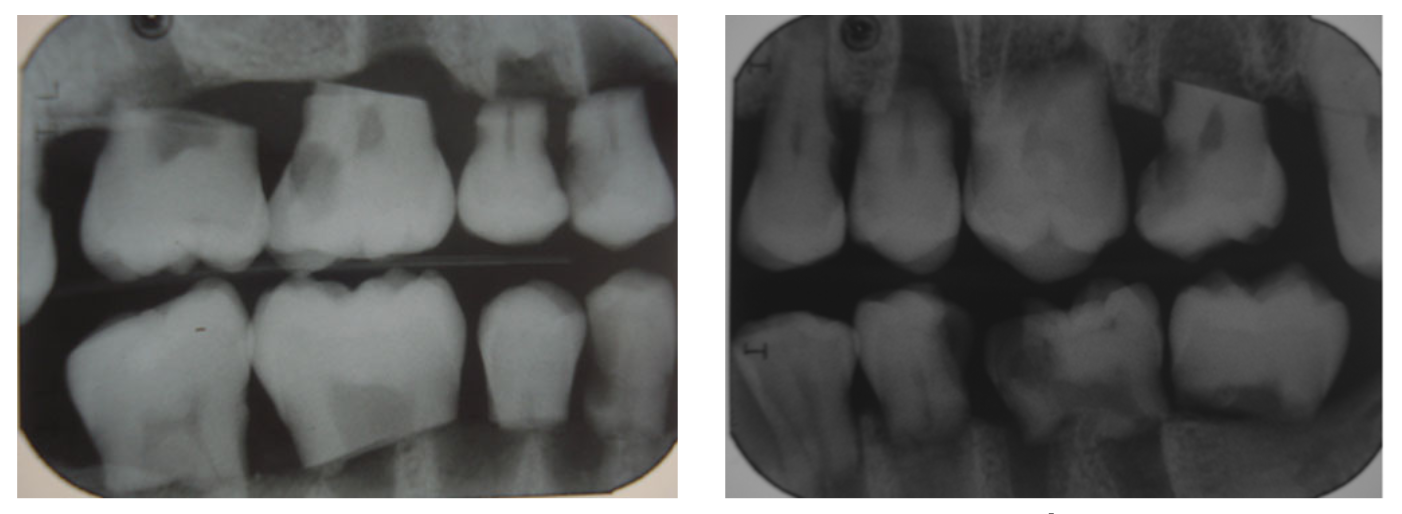

2.1 Dataset Preparation

- Sample: 발치된 인간의 소구치 및 대구치 80개를 사용하여 총 160개의 인접한 표면을 평가 대상으로 설정했다.

- Imaging Modalities:

- Ground Truth (Gold Standard): 촬영 후 치아를 물리적으로 절단하여 입체 현미경으로 충치 유무 및 진행 정도를 4단계 척도로 정밀 판독했다.